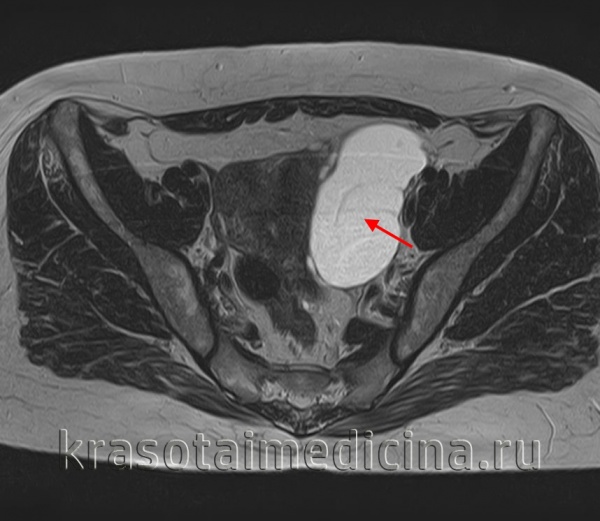

Диагностика начинается с подробного сбора анамнеза с особым вниманием к семейному, так как существует генетическая предрасположенность к развитию цистаденом. Показан осмотр в зеркалах, бимануальное ректовагинальное исследование. Проводится трансвагинальное ультразвуковое исследование, при выявленных больших размерах опухоли оно дополняется трансабдоминальным исследованием. Также возможно выполнение КТ или МРТ органов малого таза в случае подозрения на наличие злокачественного процесса или при малой информативности данных ультразвукового исследования.

В процессе гинекологического УЗИ точно устанавливаются размеры кистомы, толщина капсулы, уточняется наличие камер и сосочковидных разрастаний. При пальпации живота, а также с помощью УЗИ брюшной полости может выявляться асцит. Обнаружение опухоли яичника требует исследования онкомаркера СА-125. В ряде случаев для уточнения диагноза целесообразно проведение КТ или МРТ малого таза. Окончательное подтверждение диагноза и выяснение морфологической формы папиллярной кистомы яичника производится в процессе диагностической лапароскопии, интраоперационного гистологического исследования.

- компьютерной или магнитно-резонансной томографии (КТ или МРТ), дающих сведения о расположении, размерах, структуре, содержимом кисты яичника и ее отношении к предлежащим органам

Для объективного подтверждения наличия кистомы яичника и определения ее размеров выполняется УЗИ органов малого таза, КТ или МРТ-исследование. Характер кистомы яичника уточняется с помощью исследования крови на онкомаркер СА-125, пункции брюшной полости через задний свод влагалища с цитологическим анализом жидкости. По показаниям выполняются биопсия эндометрия, УЗИ молочных желез.

При бимануальном исследовании при достаточно большом размере опухоли можно определить ее величину, локализацию, консистенцию, характер поверхности, подвижность и др. Более информативным методом исследования является УЗИ, которое позволяет четко визуализировать содержимое опухоли, определить ее взаимоотношение с окружающими тканями, дифференцировать новообразование от миомы и других опухолей малого таза.